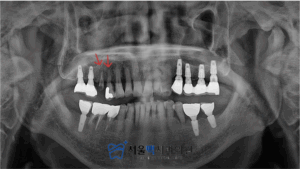

처음 내원하셨을 때, 모습인데요.

사진에 보이는 뿌리만 남은 치아는 남은 부분마져

치아우식이 진행된 상태였습니다.

그리고 옆 치아도 치아우식이 상당히 진행되었고,

치주질환까지 있어 살리기 어려울 것으로 판단되었습니다.

치아가 파절되기 전에

내원하셔서 치료를 받으셨다면,

좋으셨으리라 생각되었으나 지금에

더 나빠지지 않도록 임플란트 식립 계획을 세워드렸습니다.

서울맥치과는 치조골의 폭과 양을 3D CT 촬영을 통해

정확하게 확인하고,

적절한 임플란트 픽스쳐가 식립될 수 있도록

길이와 지름을 확인하고 진행하였습니다.